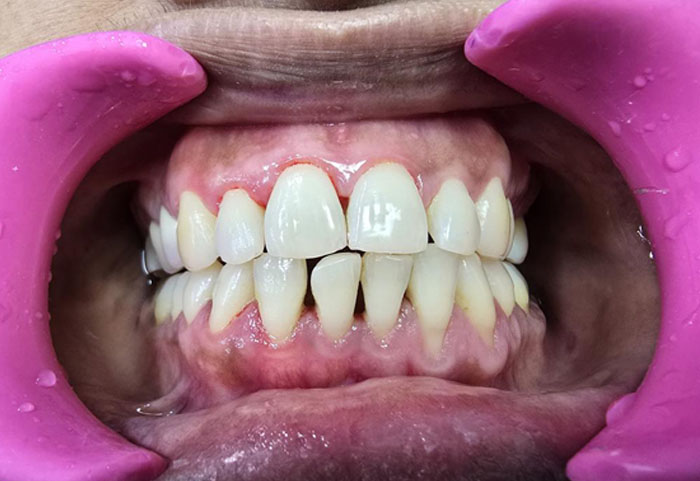

Every smile deserves gentle, thorough care—explore our EMS Guided Biofilm Therapy (GBT)

cases and see how patients leave with cleaner, healthier, and brighter smiles.

Experience painless, precision cleaning that goes beyond routine scaling and protects your teeth and gums.

See how EMS GBT can transform your oral health for you and your family.